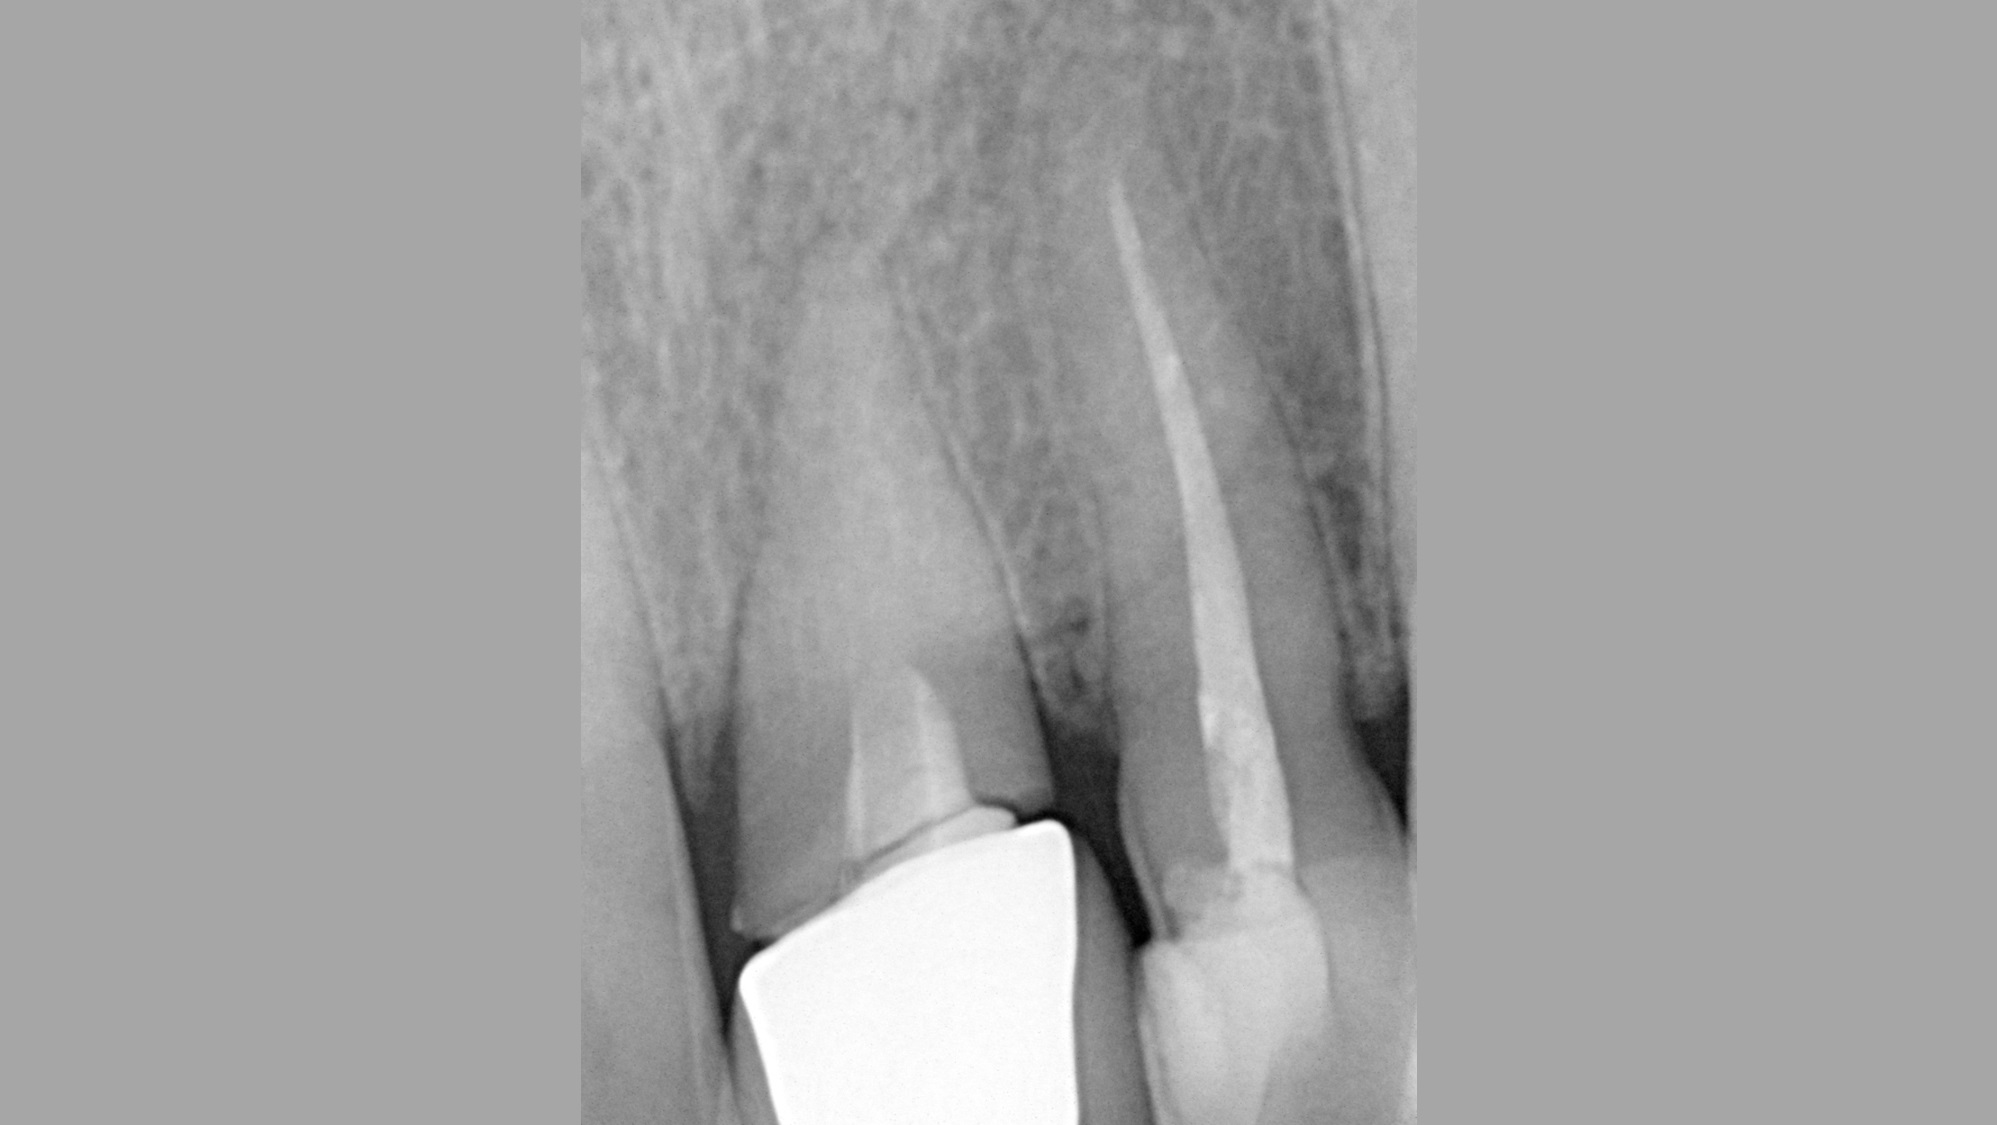

01/16 - Situation before extraction with single tooth crowns on 21 and 22

03/16 - Radiograph befor extraction of 21